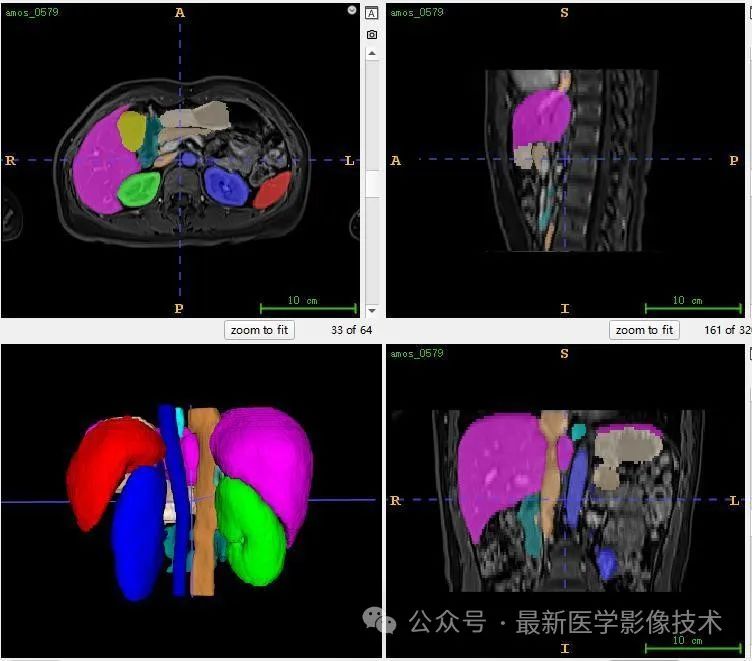

12、验证集分割结果

左图是金标准结果,右图是预测结果。

13、测试集分割结果